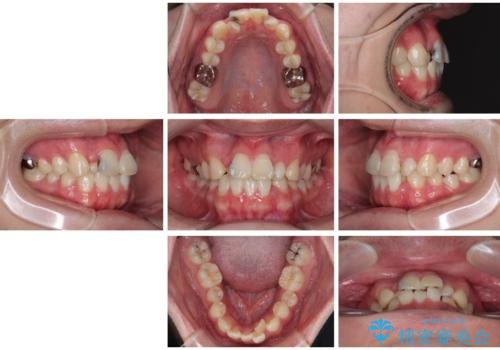

- 「歯並びがデコボコしていて、上下の中心がズレているのが気になる…」という悩みで来院された患者さまの症例をご紹介します。

初診時の状態

・上下ともに歯がきれいに並びきらず、がたつきが見られました。

・上下の前歯の中心(正中)がずれています。

・特に上顎の幅が狭いため、下顎の歯列も内側に入り込み、歯が並ぶスペースが不足していました。